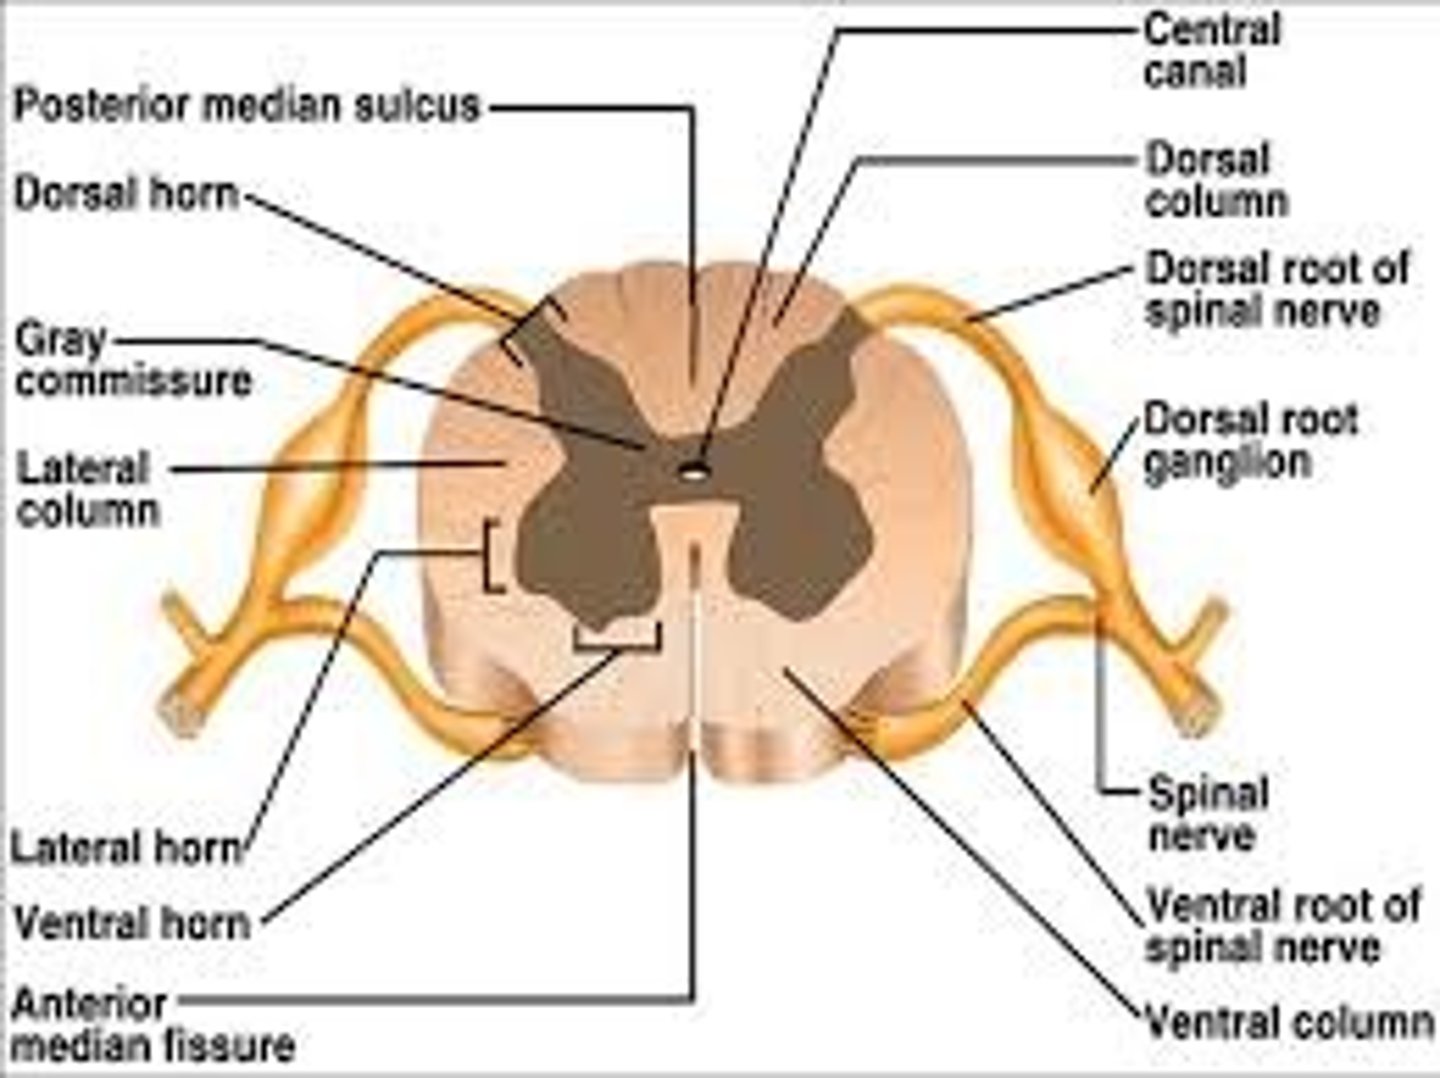

Spinal cord Anatomy (cross-sectional)

1)Internal butterfly shaped gray matter,

2)Exterior white matter,

3)Central canal filled with cerebrospinal fluid (CSF),

4)Cushioned & protected by meninges,

5)Pia mater,

6)Spinal nerves leave at the level of each vertenrae

Horns of Spinal Cord Anatomy

Dorsal Horns,

Ventral Horns,

Lateral Horns

Dorsal Horns

Lateral Horns

Ventral Horns

Interneurons

exterior white matter of the spinal cord

Ascending (sensory) and descending (motor) myelinated nerve tracts,

Posterior, anterior, lateral columns or funiculi

Posterior Columns

Anterior Columns

Lateral Columns/ funiculi

Central canal filled with what?

Central canal filled with cerebrospinal fluid (CSF)

Cushioned and protected by meninges

1) Cover the spinal cord

2) Dura mater, Arachnoid & Pia mater

dura mater of spinal cord

1) Separated from the periosteum by the epidermal space (fat, blood vessels)

2) Subdural space between dura and arachnoid mater

Dura Mater